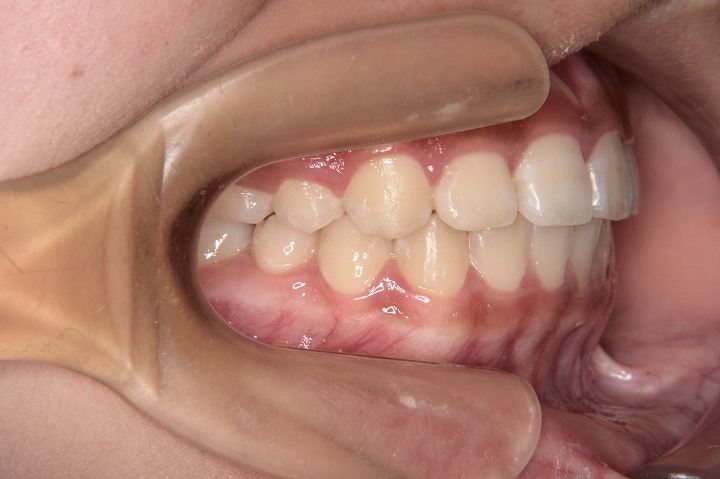

トップページ > 症例紹介 > 13歳 女性 永久歯列 抜歯 (抜歯部位:上下顎小臼歯)

歯のデコボコと口元の突出感を主訴に来院された中学1年生の患者さんです。叢生と上下顎前歯の外側への傾斜を認めたため、Eライン改善のため上下顎小臼歯抜歯ケースとしてでエッジワイズ装置を用いて配列を行っております。

初診時

動的治療終了時